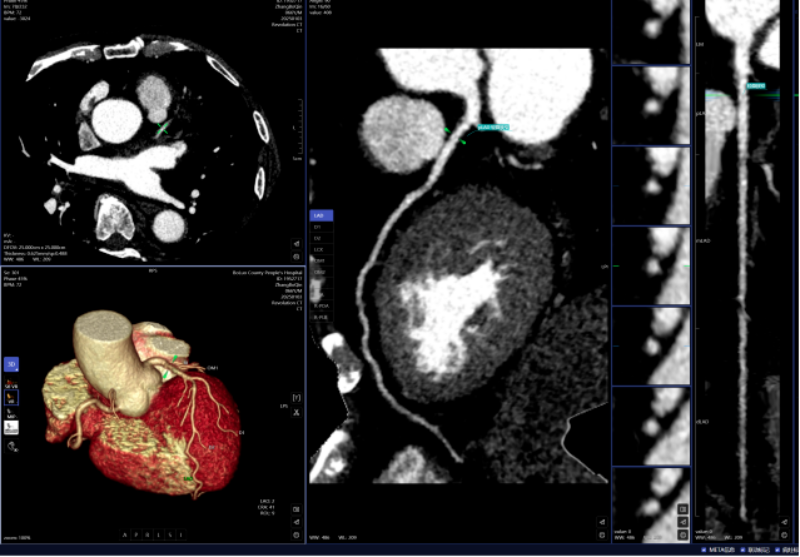

血管診斷、腦血管灌注成像

頭頸部CTA、冠狀動脈CTA、肺動脈CTA及肢體CTA是一種無創(chuàng)、低風險、快速的檢查方法,能夠清晰識別血管狹窄、畸形或斑塊,明確病灶與周圍正常組織的位置關系,為治療方案的制定提供有力依據(jù),能提高患者生存率,縮短高危患者急救救治時間。

以往,放射科醫(yī)生進行頭頸部CTA和冠狀動脈CTA重建后處理,需要醫(yī)生應用工作站手動處理,耗時約20-30分鐘。而AI人工智能輔助診斷系統(tǒng)通過計算機視覺和深度學習技術,僅需5-10分鐘即可完成影像重建的后處理計算,一鍵生成精準的三維重建圖;系統(tǒng)還能自動標記血管名稱、快速判斷斑塊性質(zhì),并根據(jù)最新指南對狹窄程度進行分級診斷等,幫助醫(yī)生快速定位病變節(jié)段,準確分析斑塊類型及狹窄程度;對腦血管灌注成像進行快速重建和診斷,大幅縮短患者等候檢查和獲取診斷報告的時間。